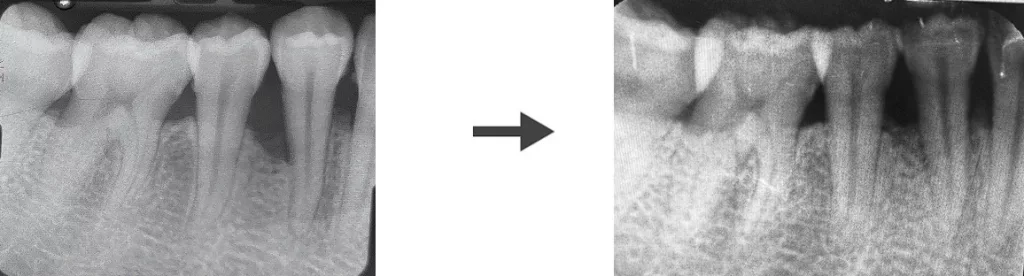

Avant l’intervention

Quelques semaines après l’intervention